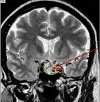

Удаление опухоли хиазмально-селлярной области

Удаление опухоли в хиазматически-седалищной области выполняется при непрерывном росте новообразования, отсутствии проводимого лучевого или гормонального лечения, прогрессирующем ухудшении зрения, компрессии новообразования третьего желудочка с нарушенным оттоком спинномозговой жидкости. При опухолях турецкого седла с небольшим выходом за его пределы операции выполняются через нос, открывающий основную грудь. При значительном прорастании новообразования в структурах, примыкающих к турецкому седлу, и в новообразованиях хиазмы используется сверление лобной кости черепа. Прорастание опухоли в кавернозном синусе увеличивает вероятность газовой эмболии и массивного кровотечения во время операции.